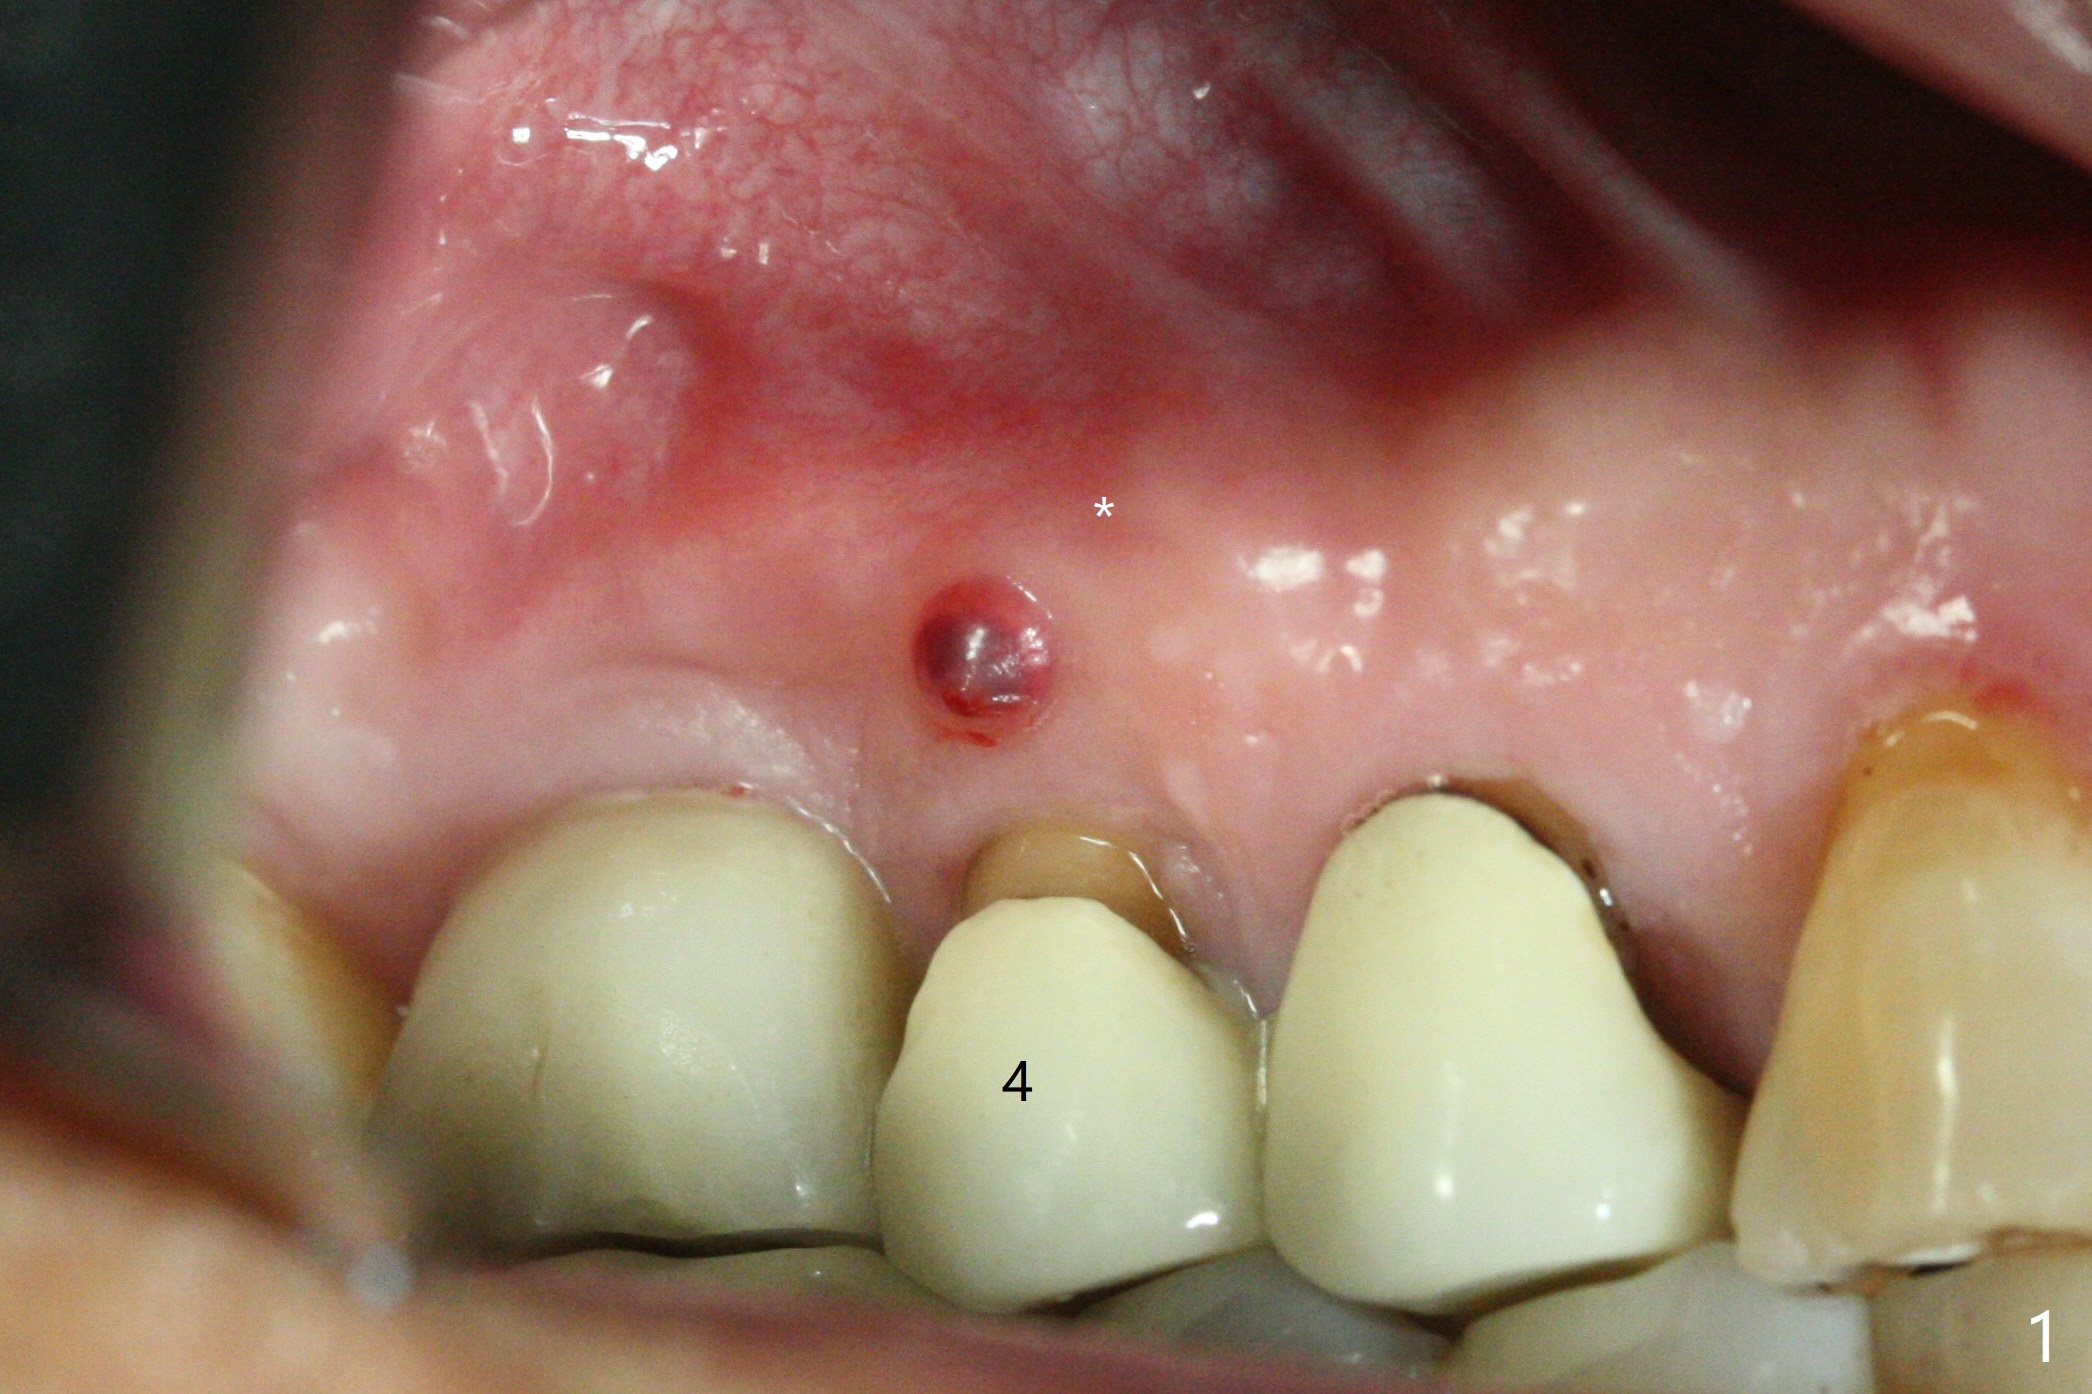

In spite of a fistula at #4, the buccal plate is present because of the exostosis (Fig.1 *). Since the socket is long and narrow, it is difficult to initiate osteotomy in the distal slope. Since the buccal plate is low, osteotomy is established as palatal as possible. The sinus floor is thin, but hard to elevate with Magic Sinus Lifter. Use of 3 mm Magic Expander leads to sinus floor break through and membrane perforation. After increase in the osteotomy with sequential expanders, a 5x20 mm tap is inserted with stability (Fig.2). Two pieces of PRF membrane are inserted for sinus membrane repair, followed by small amount of allograft (mixed with PRF, Fig.3 *) and a 4.5x17 mm dummy implant. A 5x17 mm tissue level implant is placed with >45 Ncm; with immediate placement of a 4x3 mm abutment (Fig.4), an immediate provisional is fabricated. There is no postop nasal hemorrhage. The immediate provisional has occlusal perforation 1.5 months postop. The tooth #13 has mobility due to its overuse and missing the teeth #14 and 18. Bitewing taken while redoing crown for #30 shows that the implant threads are subcrestal (Fig.5). There is no crestal bone resorption 6.5 months postop (Fig.6,7), while the periradicular radiolucency decreases (Fig.7).